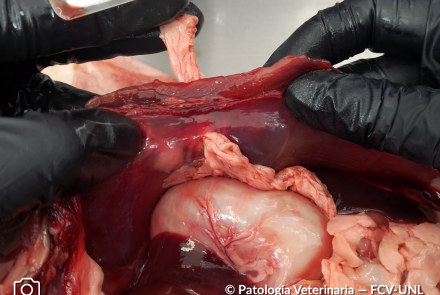

Depleción de las Placas de Peyer (GALT)

Depleción focal del tejido linfoide asociado a mucosa intestinal (GALT), correspondiente a placas de Peyer, de aspecto aplanado, color pálido y superficie lisa.

Lo podemos relacionar en este caso a una etiología infecciosa viral.

Especie: Canino